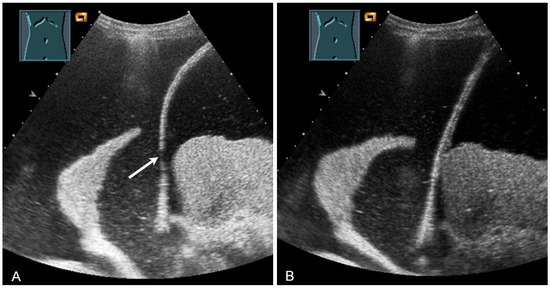

Figure 3.

A patient with suspected granulomatous lung disease and a thoracotomy performed for histologic confirmation 7 days prior to US examination. Detection of a complex mass with gas containment on B-mode US (A). On CEUS, only enhancement of the capsule is observed (B), consistent with a cytologically confirmed abscess of the chest wall. The arrows mark the abscess capsule.